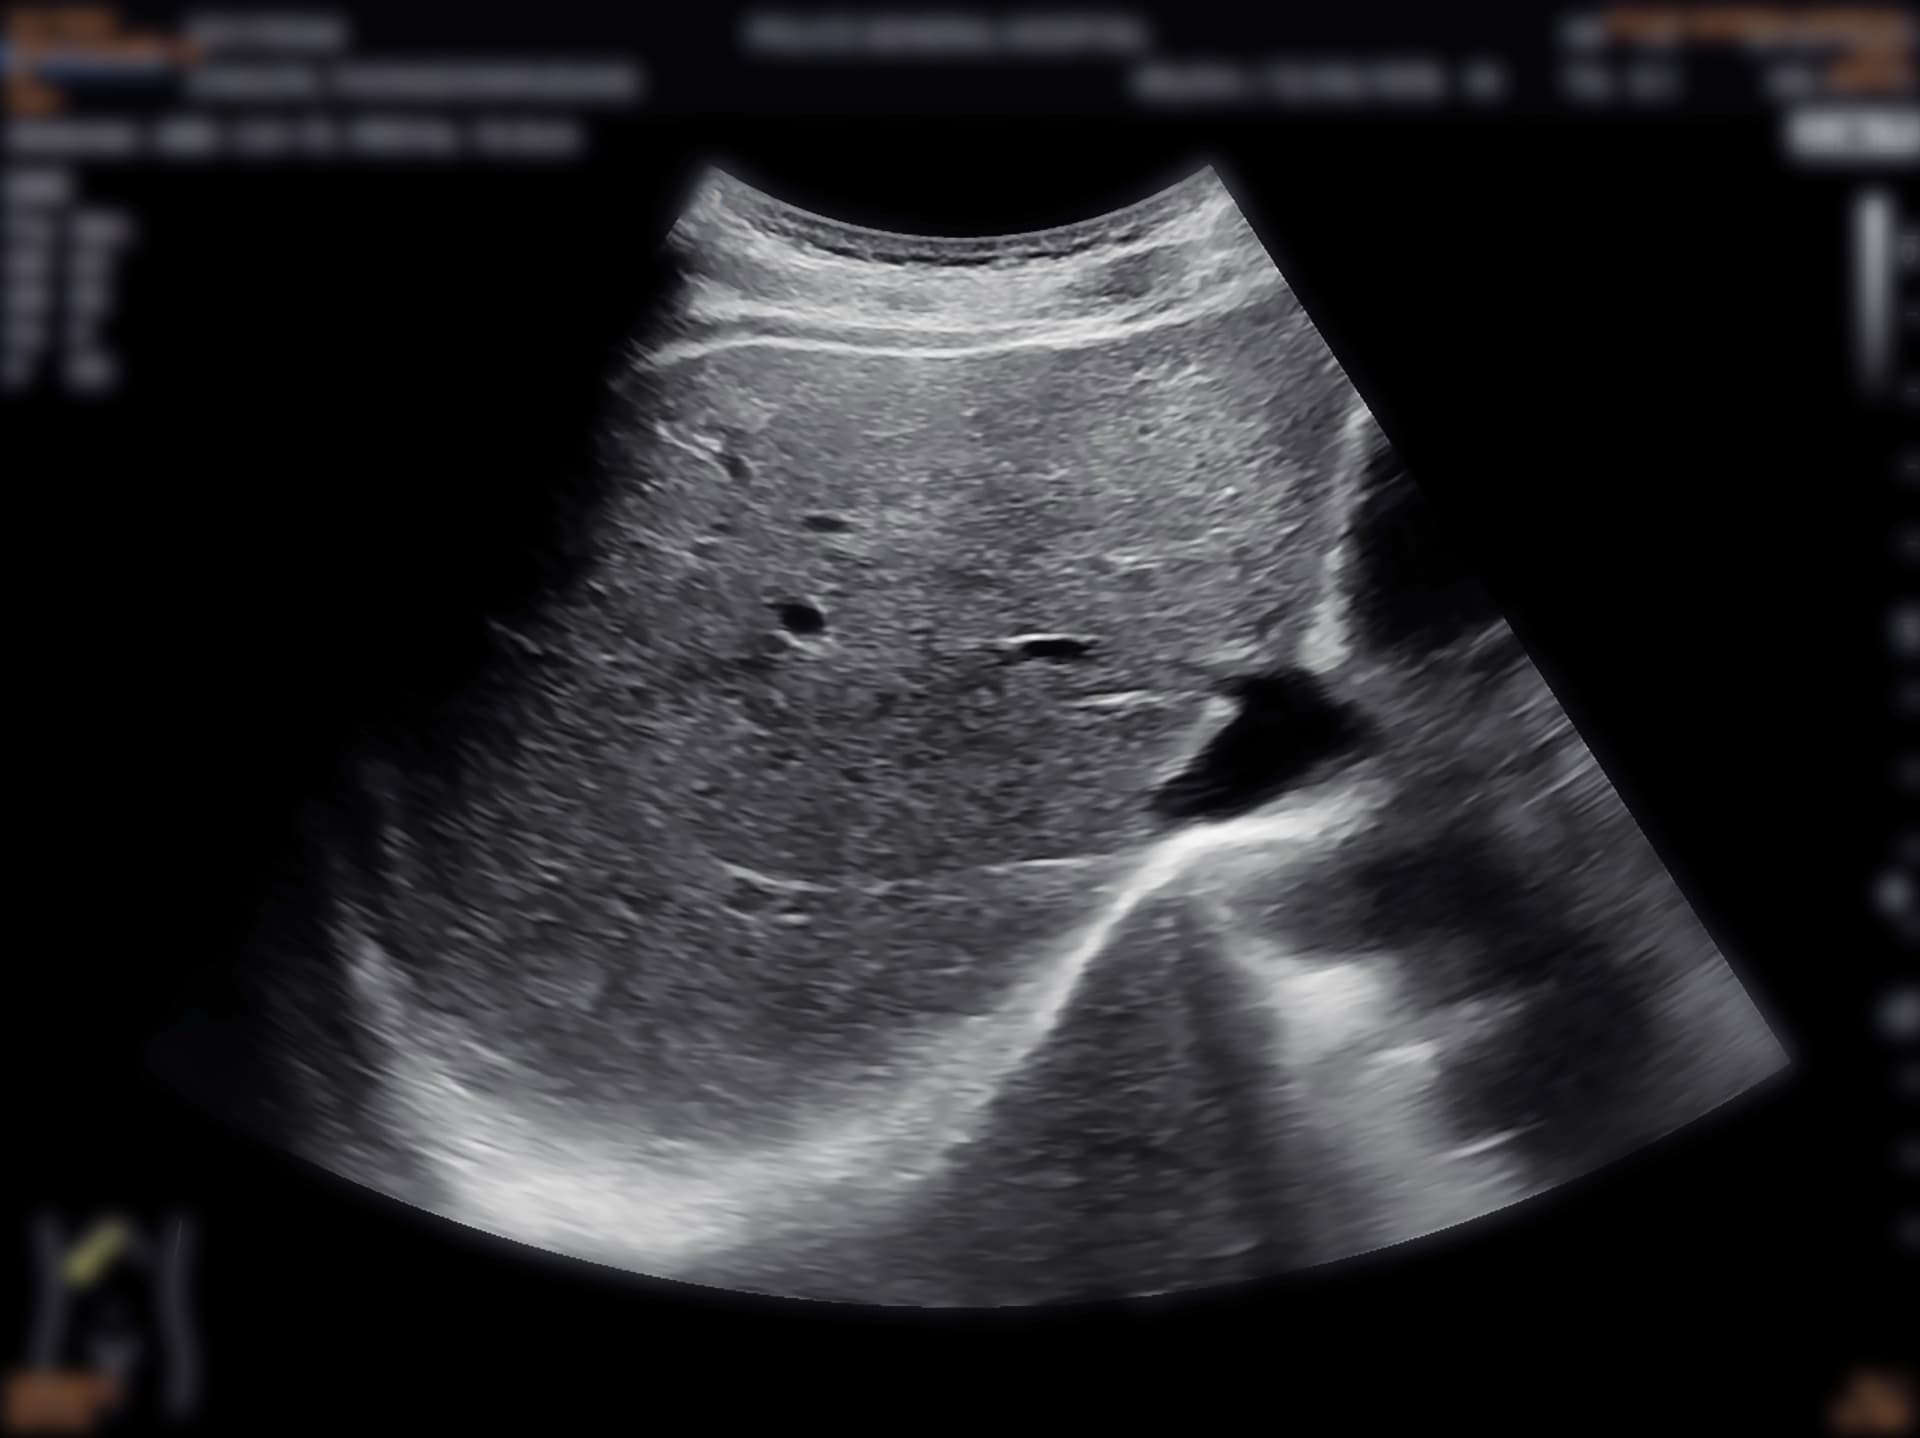

Ultrasound

Detects liver abnormalities and screens for liver cancer